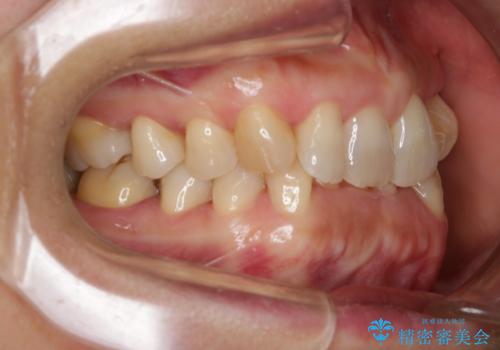

- 上下の歯のがたつきと、噛み合わせが深いことを気にされてご相談にいらした方です。噛み合わせに参加していない歯を抜歯してインビザラインにて治療を行いました。

一般的に噛み合わせの深い方へのインビザライン治療は適応が難しいとされていますが、今回は噛む力を上手にコントロールできたことと、内側に入り込んでいた前歯の角度を調整したことで下の歯がしっかり見えるようになりました。短期間で劇的に見た目が改善し、大変喜んでいただけました。